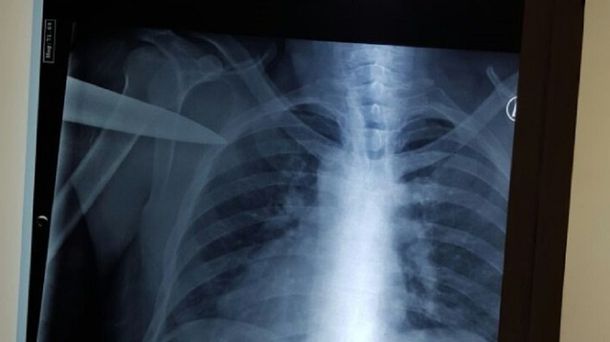

En forma inmediata se le practicó una placa para determinar la profundidad de la lesión y, sobre todo, el daño provocado teniendo en cuenta que el arma cortante se mantuvo en el cuerpo a pesar de las maniobras del hombre para movilizarse con rapidez y pedir ayuda.

Por fortuna para la víctima, el cuchillo -de importante tamaño- si bien quedó incrustado en su espalda no alcanzó a perforar el pulmón.